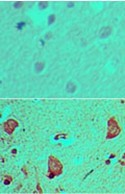

Supportive validation

- Submitted by

- Acris Antibodies GmbH (provider)

- Main image

- Experimental details

- Immunohistochemical analysis of GLI1 in formalin-fixed, paraffin-embedded human brain tissue using an isotype control (top) and AP21844PU-N (bottom) at 5 µg/ml.